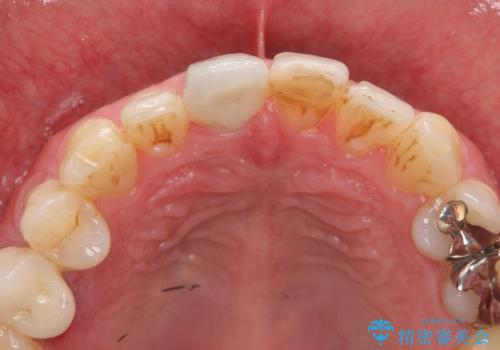

前歯の変色を改善 オールセラミック治療

- 目立つ前歯の変色の改善を希望され来院されました。

根管治療を行いそのままにしていると歯は、徐々に変色を来します。

感染の疑われる根管内に対し再度根管治療を行い、セラミッククラウンを作製することで審美性の回復します。